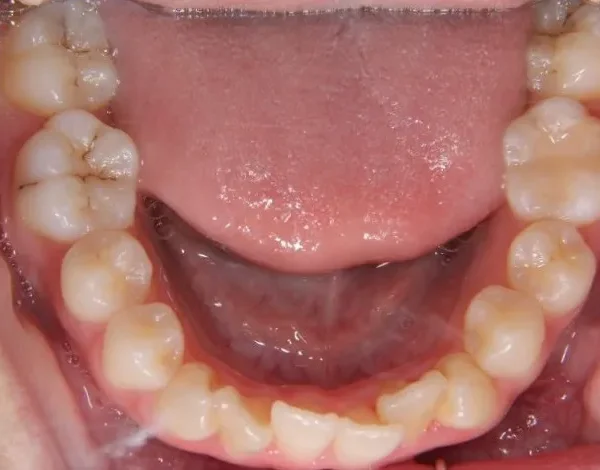

• 治療終了後

治療終了後

叢生は解消し、口元が大幅に引っ込み、下顎面高も縮小しました。

主訴が改善され、ご満足頂きました。